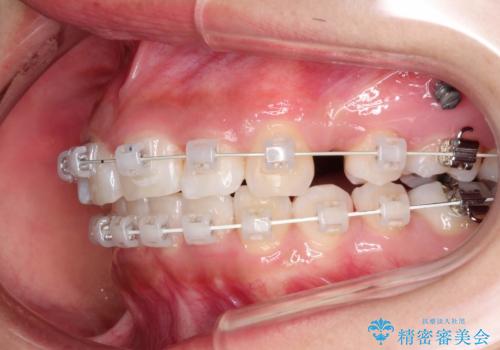

- 前歯のがたつきと出っ歯が気になるとのことで来院されました。

上顎の前から4番目の歯を両側合計2本抜歯して矯正することとなりました。

抜歯をして矯正をすることで、前歯を後方に移動させ、ガタガタを改善することができました。